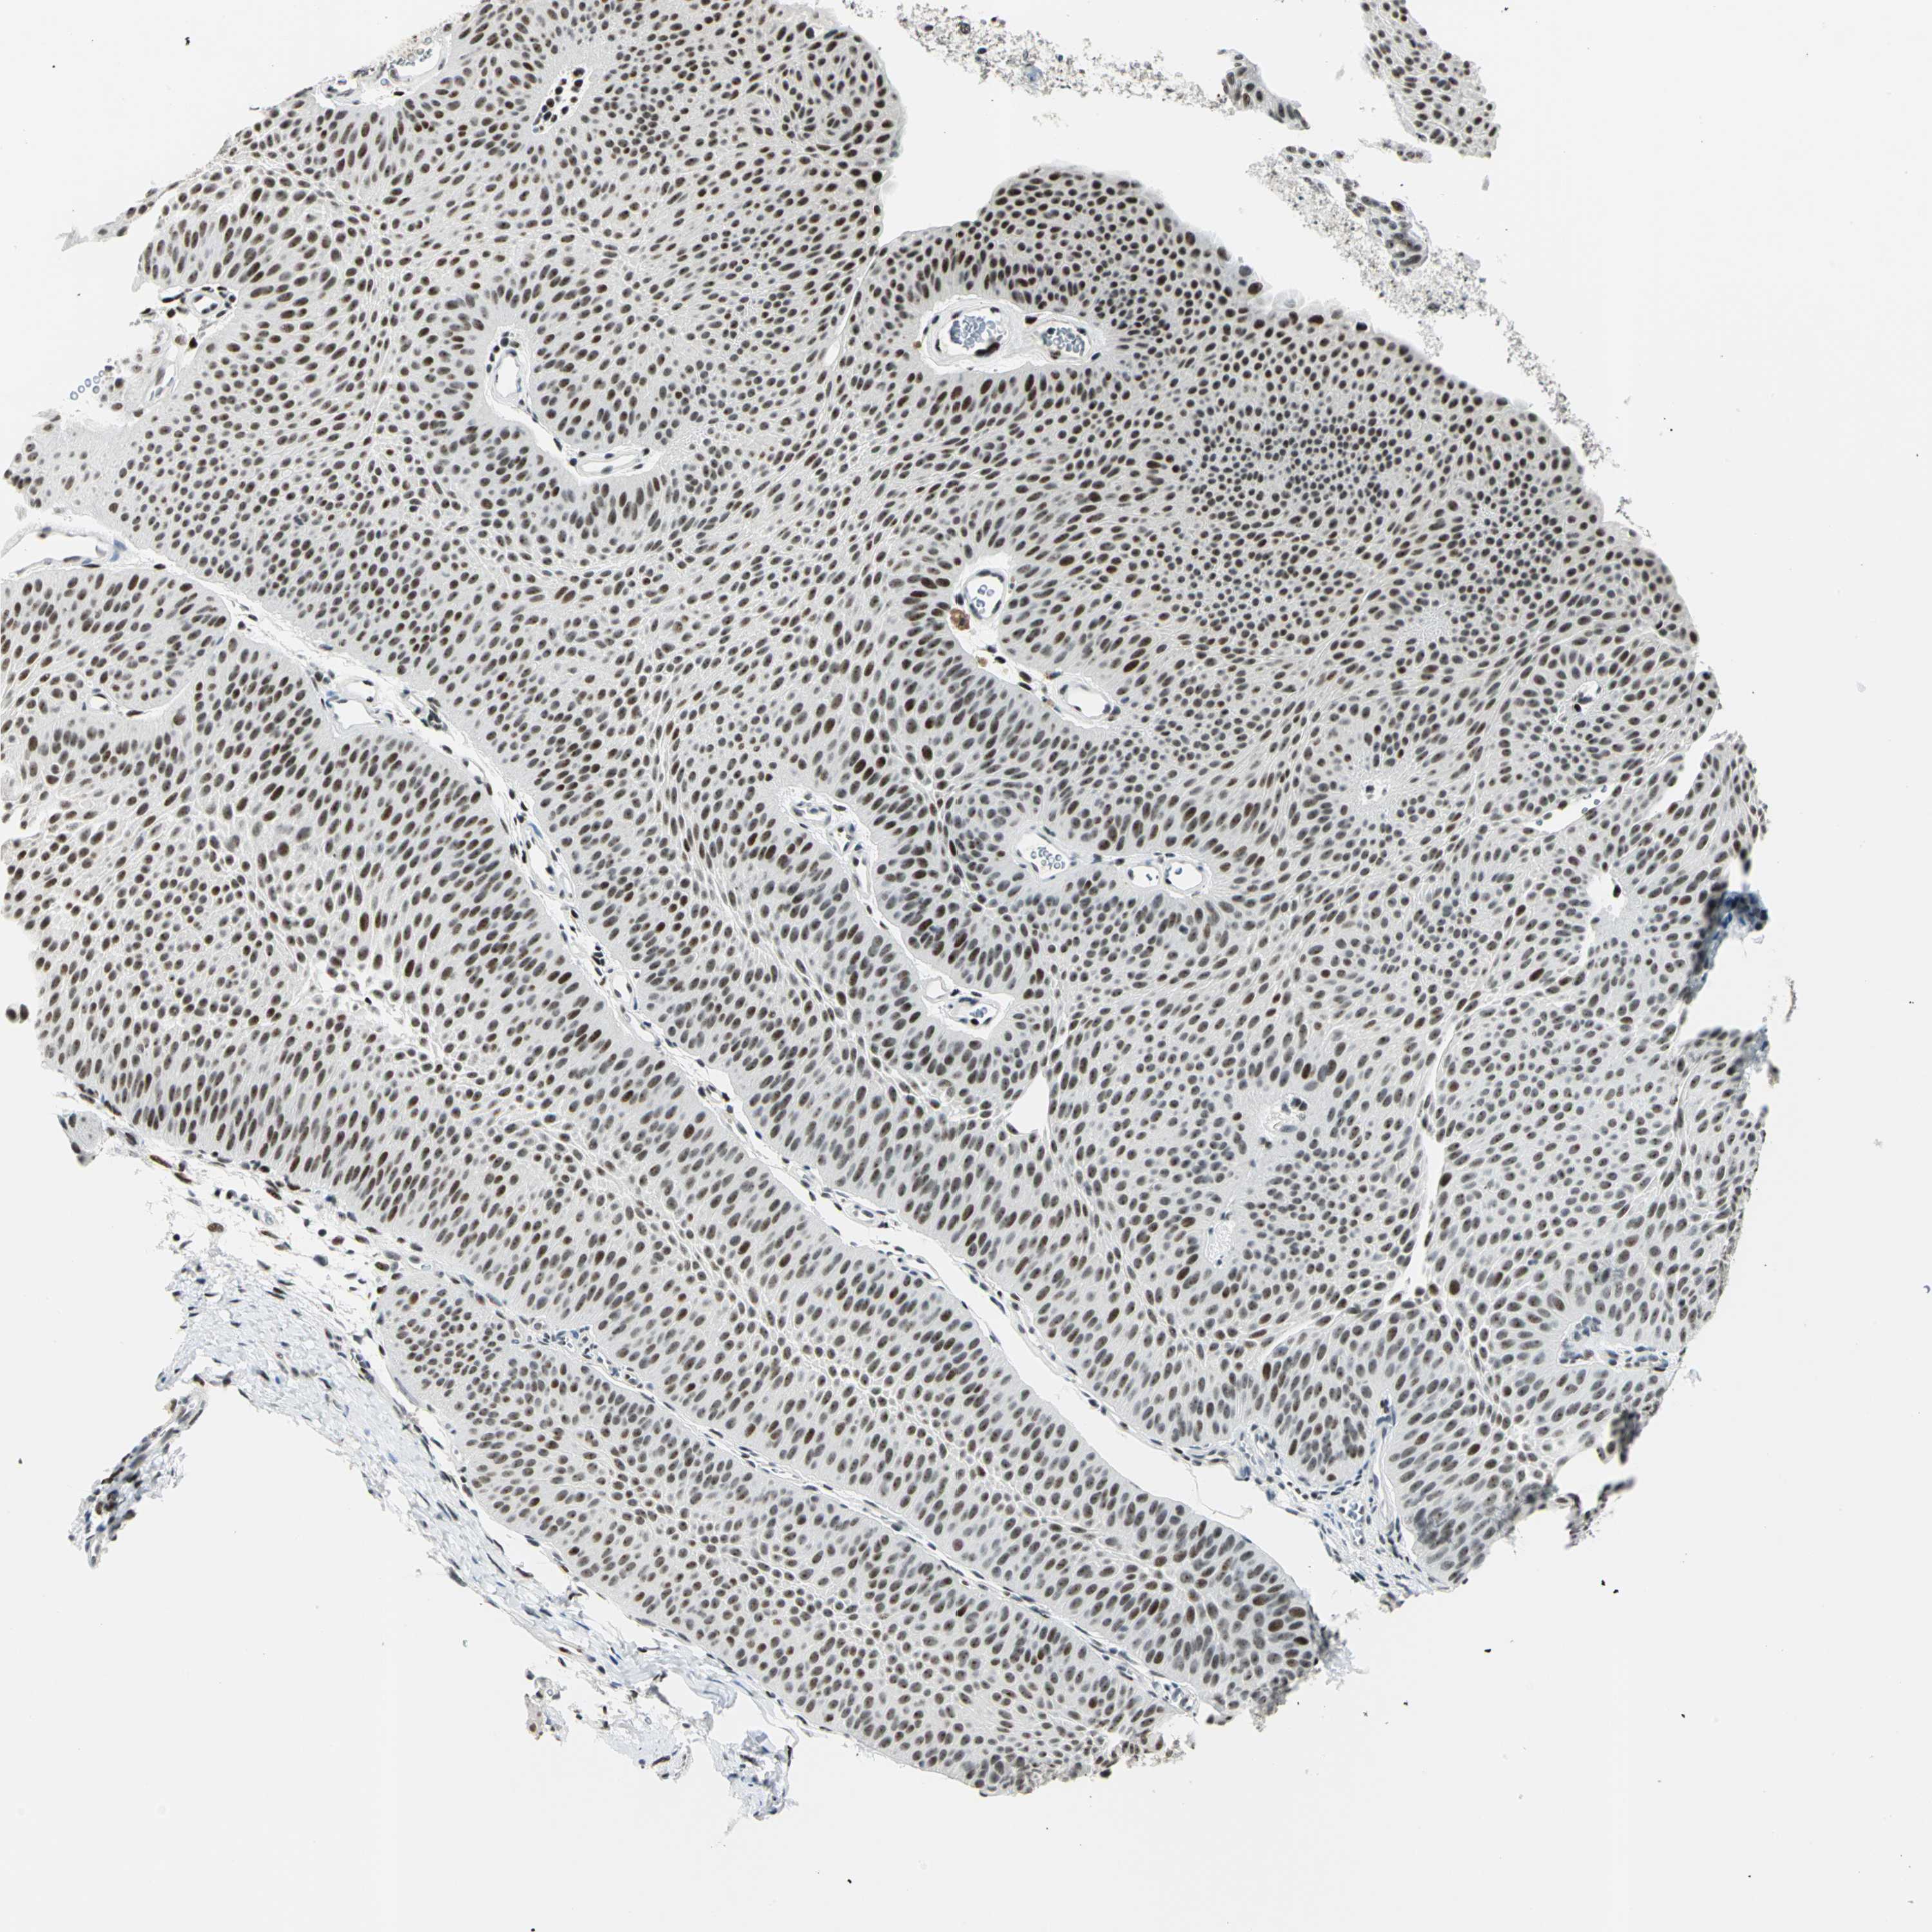

UROTHELIAL CANCER - Protein expressioni

A mouse-over function shows sample information and annotation data. Click on an image to view it in a full screen mode. Samples can be filtered based on level of antibody staining by selecting one or several of the following categories: high, medium, low and not detected. The assay and annotation is described here.

Antibody stainingi

Antibody staining in the annotated cell types in the current human tissue is reported as not detected, low, medium, or high, based on conventional immunohistochemistry profiling in selected tissues. This score is based on the combination of the staining intensity and fraction of stained cells.

Each image is clickable and will lead to virtual microscopy that enables deeper exploration of all samples and also displays staining intensity scores, fraction scores and subcellular localization as well as patient and tissue information for each sample.

Antibody HPA006104

Staining

High

Medium

Low

Not detected

Intensity

Strong

Moderate

Weak

Negative

Quantity

>75%

75%-25%

<25%

None

Location

Nuclear

Cytoplasmic/membranous

Cytoplasmic/membranous,nuclear

Urothelial carcinoma, Low grade

Urothelial carcinoma, High grade